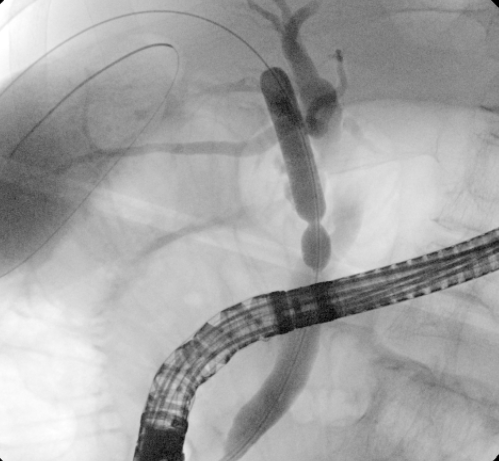

我院李虎城主任医师接诊阅片后,综合评估老人的病情,最终决定为老人行内镜下胆囊胆管取石术+胆囊引流管置入术术中见胆总管扩张,胆囊及肝内胆管正常显影,见胆总管粘膜基本正常,可见多发小碎石,沿导丝经胆囊管进入胆囊,胆囊内见大量泥沙样小颗粒结石、胆汁黏稠,胆囊壁未见明确新生物大量生理盐水冲洗胆囊,见墨绿色泥沙样胆汁流出。退出胆道子镜,取石球囊取出胆总管内结石。手术过程顺利,术中生命体征平稳,术后安返病房。术中字母镜图像如下